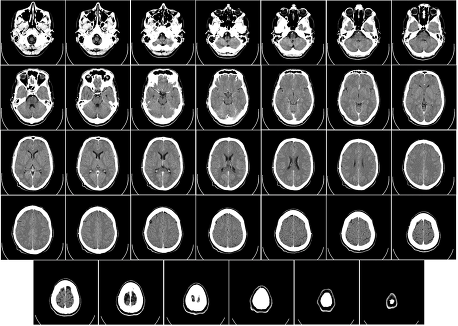

우리가 흔히 평면에 여러 점들로 구성된 이미지를 픽셀(pixel)이라 부르듯이, 3D 공간에 표현된 단위 요소를 복셀(Voxel)이라고 하는데 복셀이 이에 해당된다고 할 수 있다(마인크래프트의 블록을 생각하면 이해가 쉬울것이다). 일상적인 예로는, MRI나 CT 스캔 이미지처럼 연속적인 인체 데이터를 샘플링하여 저장하는 경우가 이에 해당한다고 볼 수 있다.

그럼 해당 데이터로 어떻게 3D표현을 할 수 있을까? 가장 단순하게는 그냥 해당 데이터들을 하나씩 그려서 쌓아줄 수 있겠다. 해당 방식을 Texture Slicing이라고 하며 가장 기본적인 Volume redering의 방법이다.